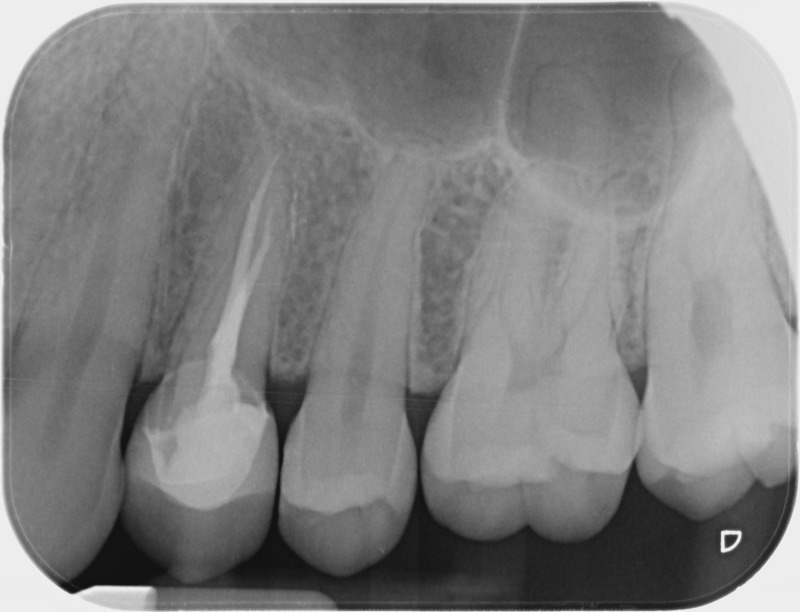

• Reprise de traitement endodontique : La manœuvre consiste à retourner à l’intérieur des racines d’une dent déjà traitée. Il arrive occasionnellement qu’une nouvelle inflammation se déclare suite à une reprise de carie ou une fracture de la dent, ou si le premier traitement endodontique est incomplet. Après s’être assuré que la dent lésée était conservable, il convient de désinfecter de nouveau le réseau canalaire parfois très complexe. La nouvelle obturation des canaux devra être protégée aussi rapidement que possible pour éviter une éventuelle contamination bactérienne.

Avant

Après